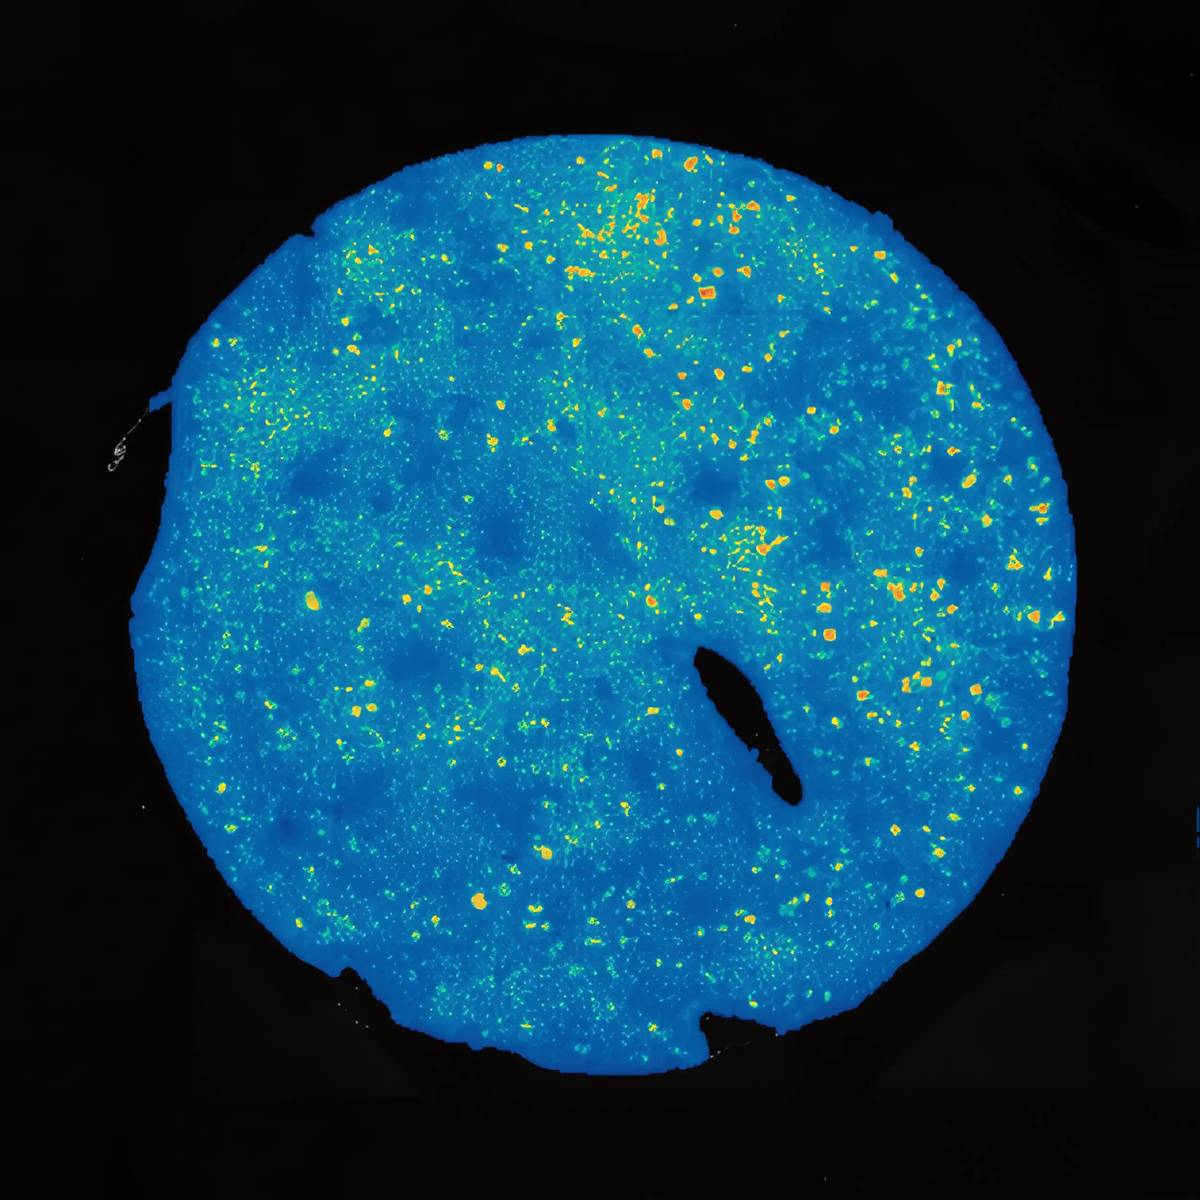

Sample Origin: human kidney

Platform: Stereo-seq OMNI